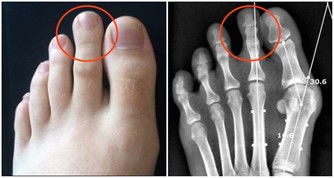

一個很明顯的信號能夠驗證,人的足部有一個明顯能摸到脈息的方位,即是足背正中最高點,輕摸能感遭到脈動。假如是輕度下肢動脈阻塞的人來說,能摸到足部脈息,證實動脈血一向通到足背部。可走了一段路後,再摸,就摸不到脈息了,這時,很可能發作了動脈血管阻塞。

把腳舉高,45度,2分鐘,仔細觀察兩條腿。假如一條腿呈蒼白,乃至是蠟白,腿部肌膚出現透明狀,待腿拿下來後,康復正常坐姿,假如這條腿出現微紅,這就闡明這條腿現已缺血了。